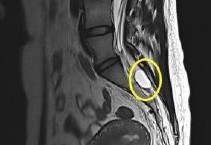

Dve najviac bežne používané a efektívne zobrazovacie metódy pre vyšetrenie Tarlovovej cysty sú MRI a CT.